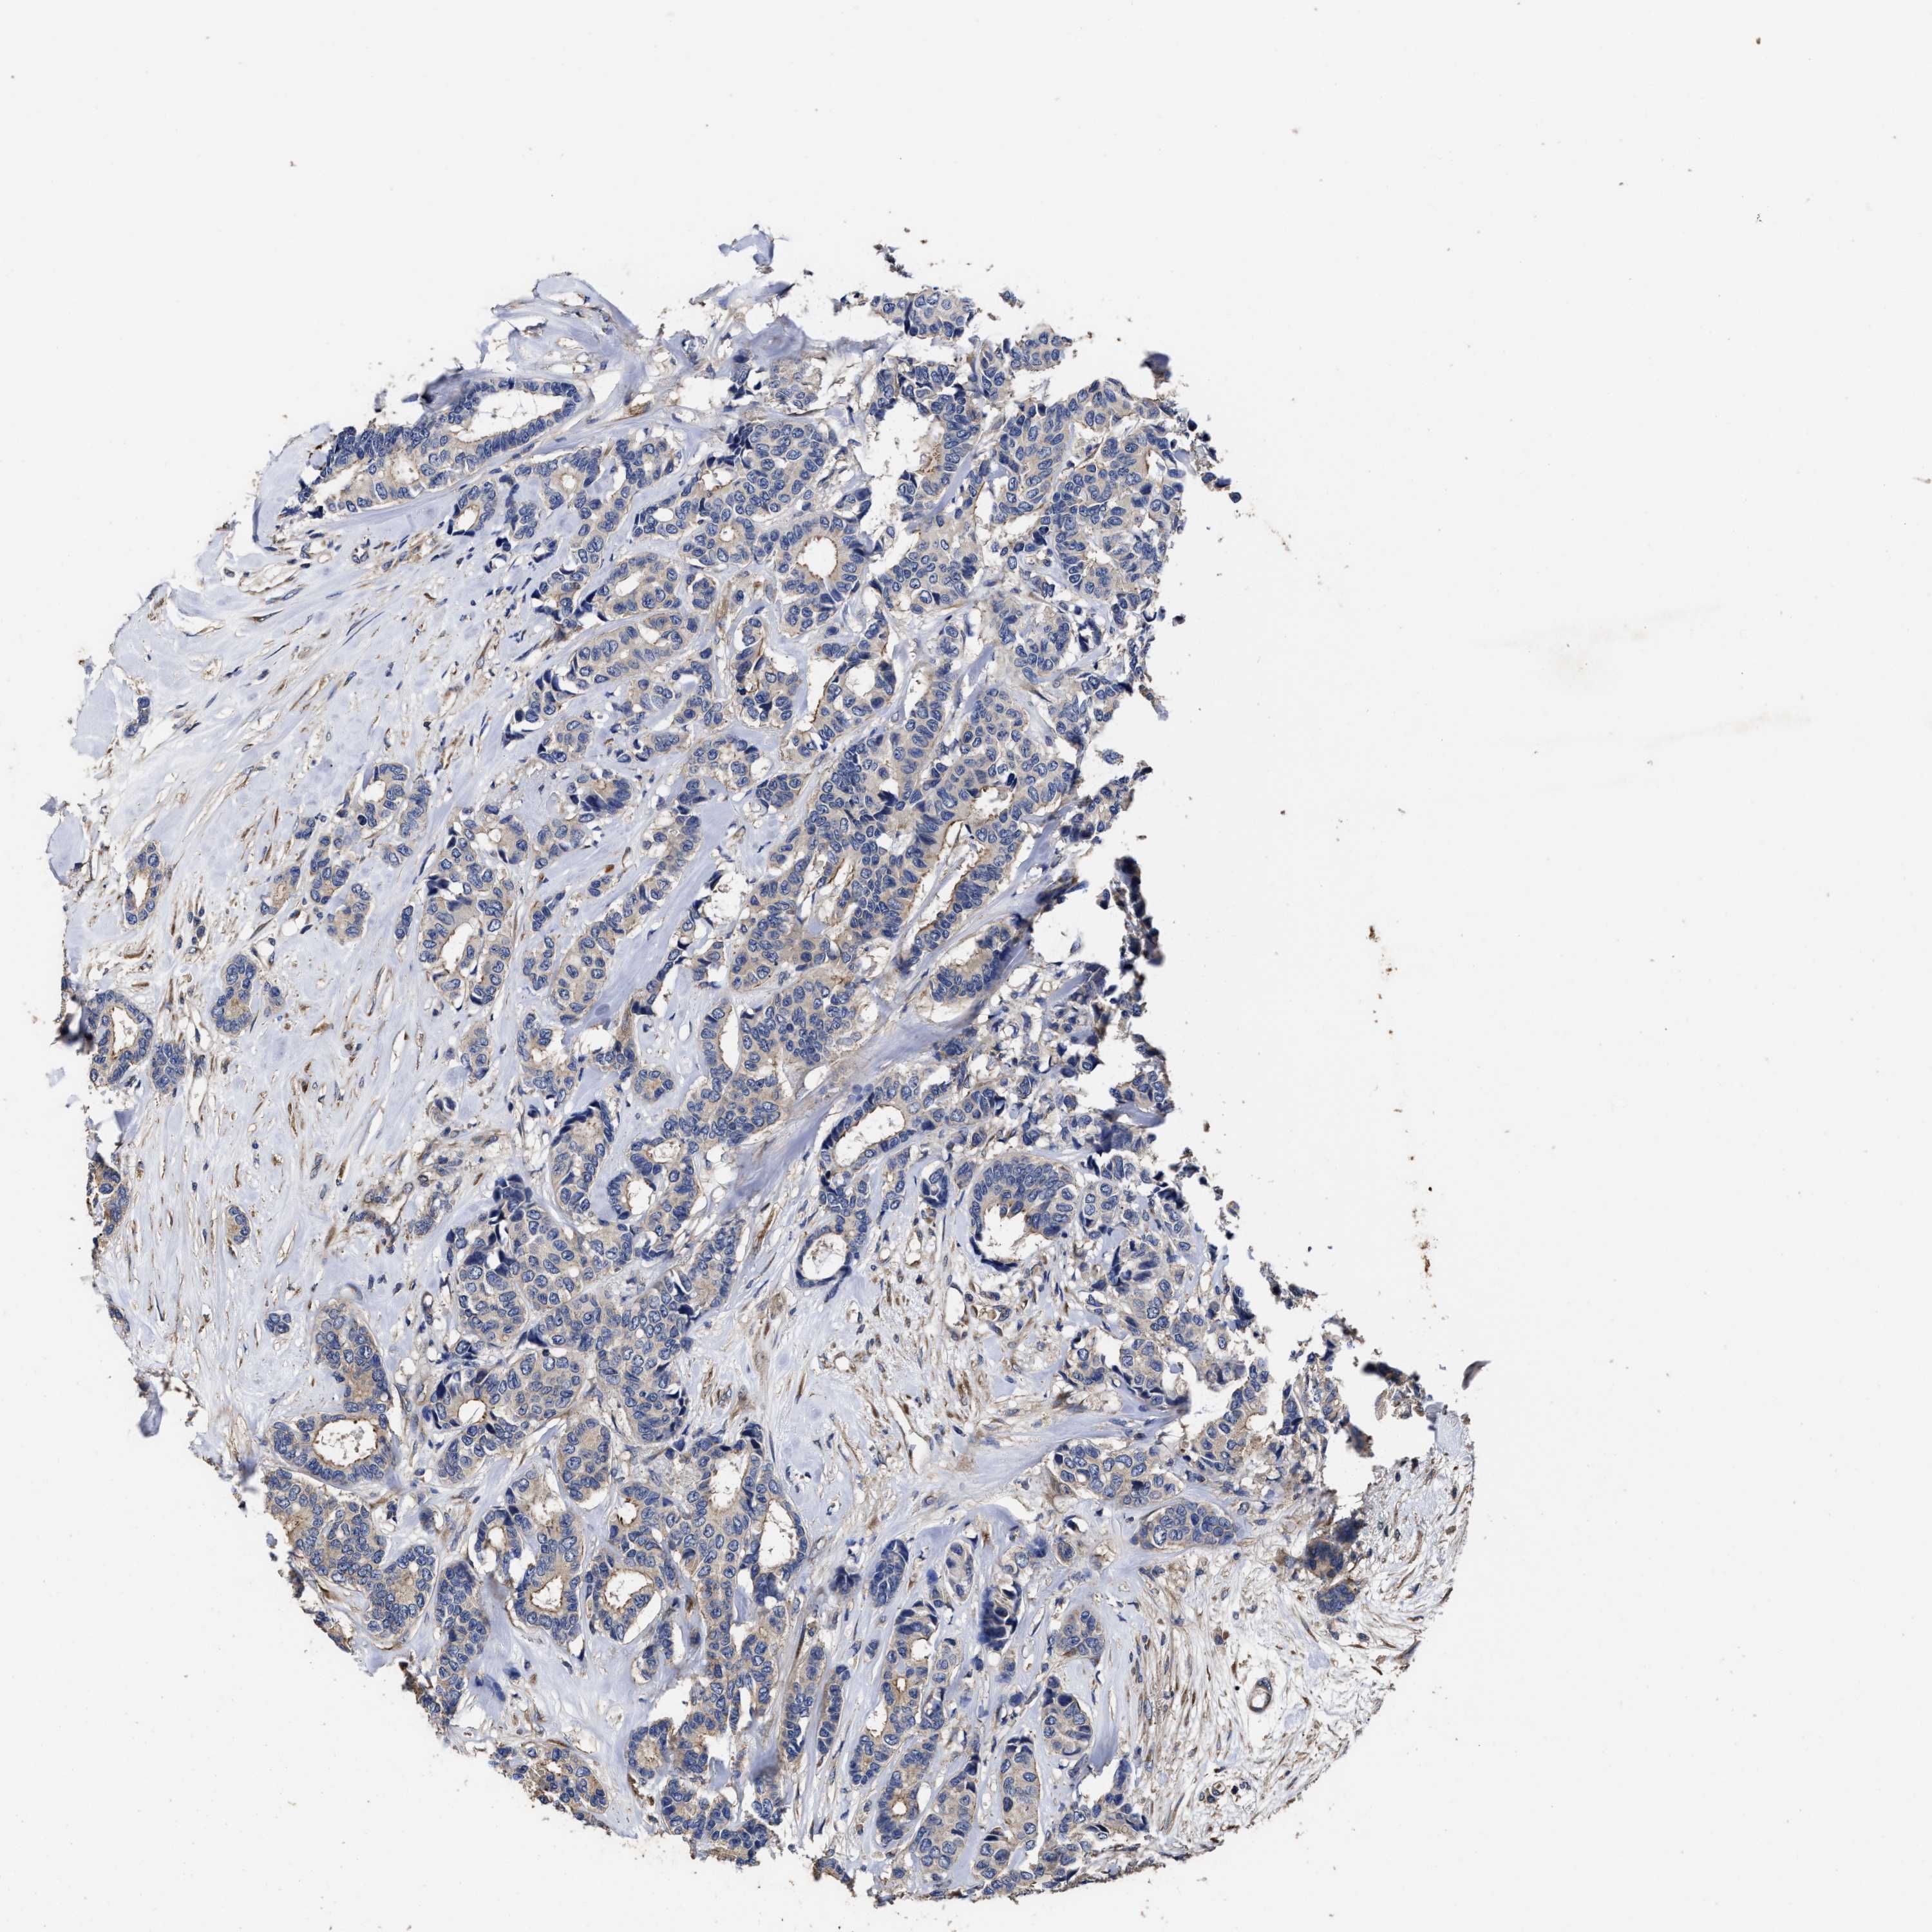

CANCER BREAST CANCER Show tissue menu

BRCA TCGA BRCA VALIDATION PROTEIN EXPRESSION